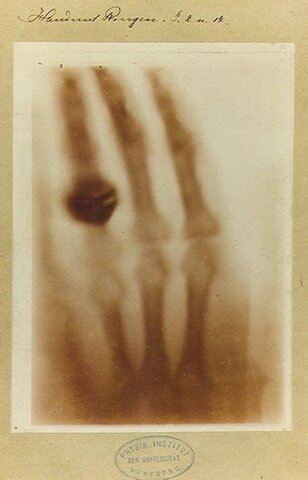

En 1895, el físico alemán Wilhelm Conrad Röntgen

descubrió una nueva forma de radiación que la llamó

“radiación X, luego de esto se empezo a implemetar el radiodiagnostico que consiste en utilizar los rayos X procedentes de una fuente externa para obtener las imágenes del interior del cuerpo. Estas imágenes son las radiografías. La imagen que se ve en una radiografía la forman diferentes tonalidades que van del blanco al negro.

Los rayos x surgieron en Hamburgo-Alemania de forma accidental por Wilhelm Conrad Röntgen ya que a medida que realizaba experimentos con tubos de vacío y un generador eléctrico descubrió que este haz de luz es capaz de atravesar la materia lo cual comprobó con la ayuda de su dama, la famosa Berta, pasó la mano por una placa en la que se proyectaban rayos x.

el alemán, Wilhelm Röntgen, nacido el 27 de marzo de 1845 por el descubrimiento de un nuevo tipo de radiación, los rayos Röntgen o, como le agradaría a su descubridor que los llamáramos, rayos X. recibio en 1901 el premio nobel en reconocimiento a los servicios extraordinarios que ha rendido al descubrir los insólitos rayos que llevan su nombre.